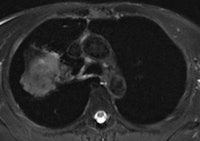

A 50-year old male patient with NSCLC stage pT2b pN2 cM0, imaged with FDG-PET/CT-MR. On coronal PET maximum intensity projection (MIP) image, an FDG-avid tumor in the right upper lobe and a mediastinal lymph node metastasis are seen. All images courtesy of Dr. Martin Huellner.For many years, PET/CT has been the standard modality for staging NSCLC patients. So, before PET/MRI can supplant it for this application, some basic clinical questions need to be addressed, said lead author Dr. Martin Huellner from University Hospital Zurich.

The imaging protocol consisted of whole-body PET/CT-MR (Discovery 690, GE Healthcare, 3-tesla MRI system MR 750w, GE). The MRI protocol included whole-body coronal short-tau inversion recovery (STIR) for eight minutes, followed by axial whole-body LAVA-Flex acquisition for three minutes and thoracic axial periodically rotated overlapping parallel lines with enhanced reconstruction (PROPELLER) imaging for five minutes. Total MRI acquisition time was approximately 16 minutes.